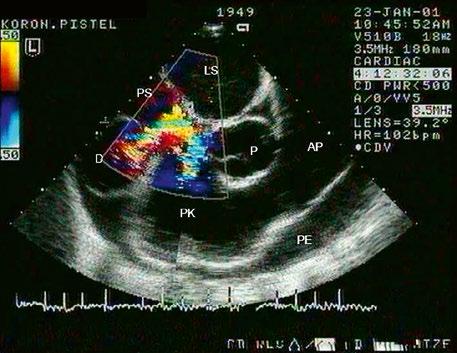

Poslechový nález kromě fixního rozštěpu 2. ozvy mívá i systolický šelest na hrotu při mitrální insuficienci. Suverénní je echokardiografická diagnostika (Obr. 45.14, Obr. 45.15, Video 45.10, Video 45.11, Video 45.12, Video 45.14), včetně jícnové echokardiografie (TEE) a trojrozměrného zobrazení (3DE), které upřesní nejen velikost síňové složky defektu, ale přítomnost komorové složky defektu či jiných zkratů,

abnormalit mitrální chlopně, nejčastěji „rozštěpu“ předního cípu (Obr. 45.20, Obr. 45.21, Video 45.15, Video 45.16), abnormálních úponů mitrální chlopně, přítomnost subaortální stenózy a jiných abnormalit. Katetrizaci doplňujeme při podezření na plicní hypertenzi, zvláště u kompletních AVSD, při neinvazivním odhadu systolického tlaku v plicnici nad 40 mmHg.(7) Srdeční magnetická rezonanace (CMR) se uplatní při